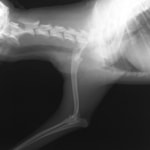

■ミニチュアダックスフント 1歳 去勢オス

前肢の成長板早期閉鎖、前肢の重度の外反変形が認められました。

関節面の変形が重度に認められます。